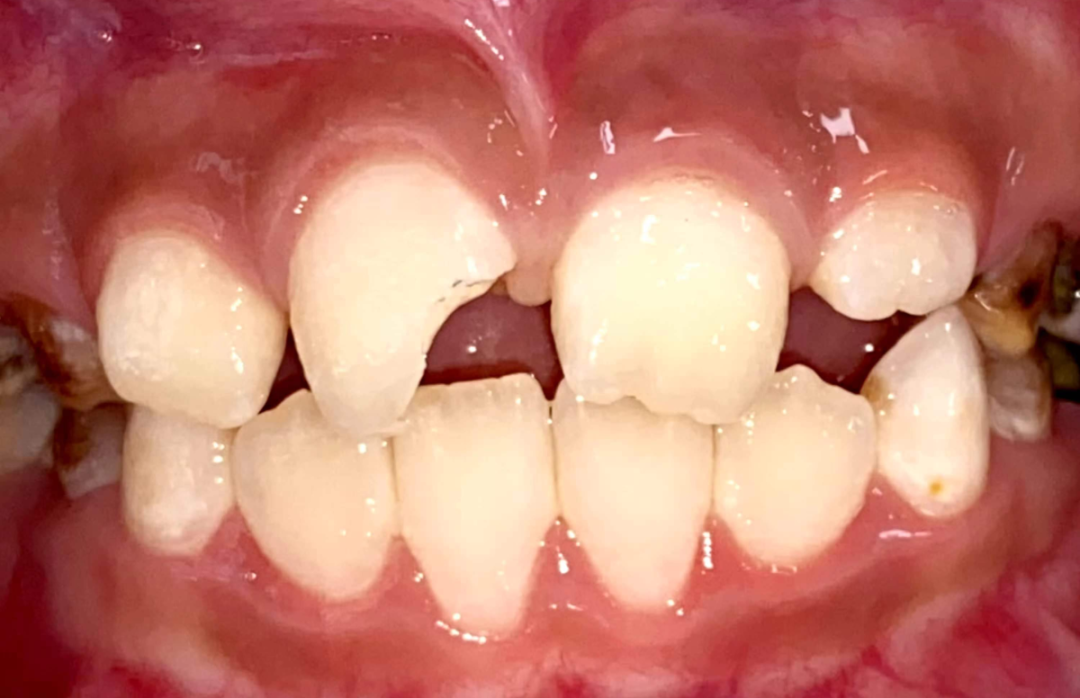

2、阻断矫治。当错颌畸形发生的早期,通过简单的方法进行早期矫治,阻断错颌畸形的发展,并引导面部向正常发育方向发展,常称阻断矫治。如早期前牙拥挤(牙弓缩窄等)使用扩弓矫治器矫治,早期牙源性前牙反合使用简单合垫舌簧矫正器矫治。

3、一般矫治。根据不同牙颌面畸形选用各类矫治器,一般矫治是口腔正畸矫治中最多见的。如可摘矫治器、功能矫治器、固定矫治器等。近年来,无托槽隐形矫治技术因其美观、舒适的优势渐渐得到人们的青睐,随着口腔正畸医疗技术及材料的不断发展,无托槽隐形矫治技术越来越成熟。目前,大部分错颌畸形可通过无托槽隐形矫治技术纠正。

金属自锁托槽矫治技术

治疗前                        治疗后

儿童错合畸形早期矫治是阻断影响儿童颌骨、牙齿正常发育的因素,促进颌面部正常发育,降低II期矫正的难度,减少II期矫正的时间,甚至不需要II期矫正。让孩子早期获得自信,绽放灿烂笑容。

术前→术后